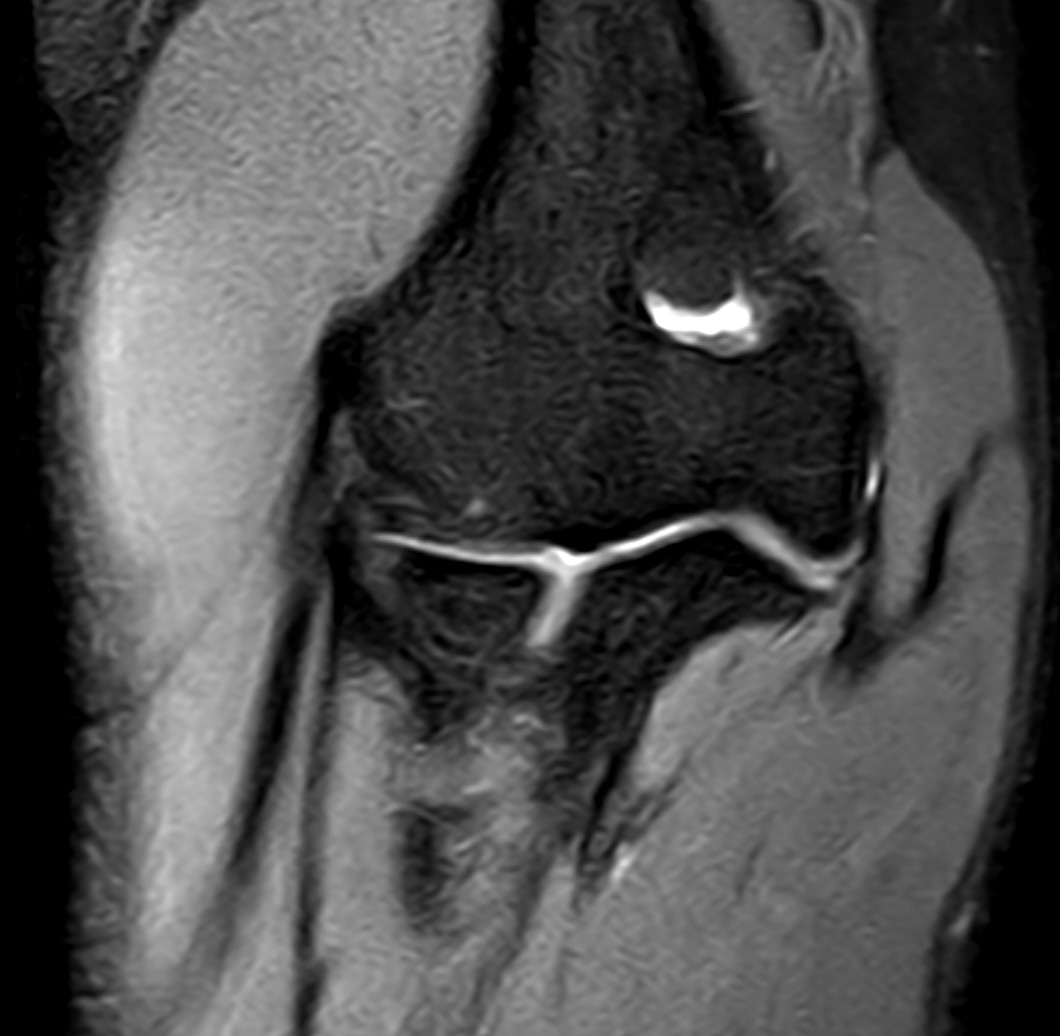

Elbow pain and related symptoms may arise from various causes, ranging from mild overuse to joint inflammation or nerve compression. Magnetic resonance imaging (MRI) is particularly valuable when other diagnostic methods like X-ray or ultrasound have not provided clear answers. MRI offers detailed images of both bone and soft tissue, making it possible to identify early changes or hidden injuries.

- Tennis elbow (lateral epicondylitis) – an overuse injury where tendon attachments on the outer elbow become inflamed. MRI can confirm the diagnosis and show the extent of tendon and soft tissue involvement.

- Golfer’s elbow (medial epicondylitis) – similar to tennis elbow but located on the inner side of the elbow. MRI helps rule out other structural issues and assess the degree of inflammation.

- Inflammatory joint diseases (arthritis or bursitis) – in suspected cases of rheumatoid arthritis or bursitis, MRI can identify swelling, joint fluid, synovitis, and other early inflammatory changes.

- Nerve entrapment – such as ulnar nerve compression at the elbow (cubital tunnel syndrome), which can cause numbness, tingling, and weakness in the forearm and hand. MRI can visualize nerve compression or surrounding swelling.

- Degenerative changes and osteoarthritis – MRI reveals cartilage loss, joint space narrowing, and other degenerative changes that may not be visible on standard radiographs.

- Tendon and muscle injuries – including partial tears, full ruptures, or chronic overuse at tendon insertions. MRI provides a clear view of the extent and location of the injury.

- Cartilage or ligament injuries – may occur with twisting injuries or trauma. MRI is superior in detecting such injuries, especially if they are subtle or not visible with other imaging methods.

- Calcific deposits or fluid accumulation – MRI can detect calcium deposits in tendons and bursae, as well as localized fluid collections that may cause pain and restricted movement.